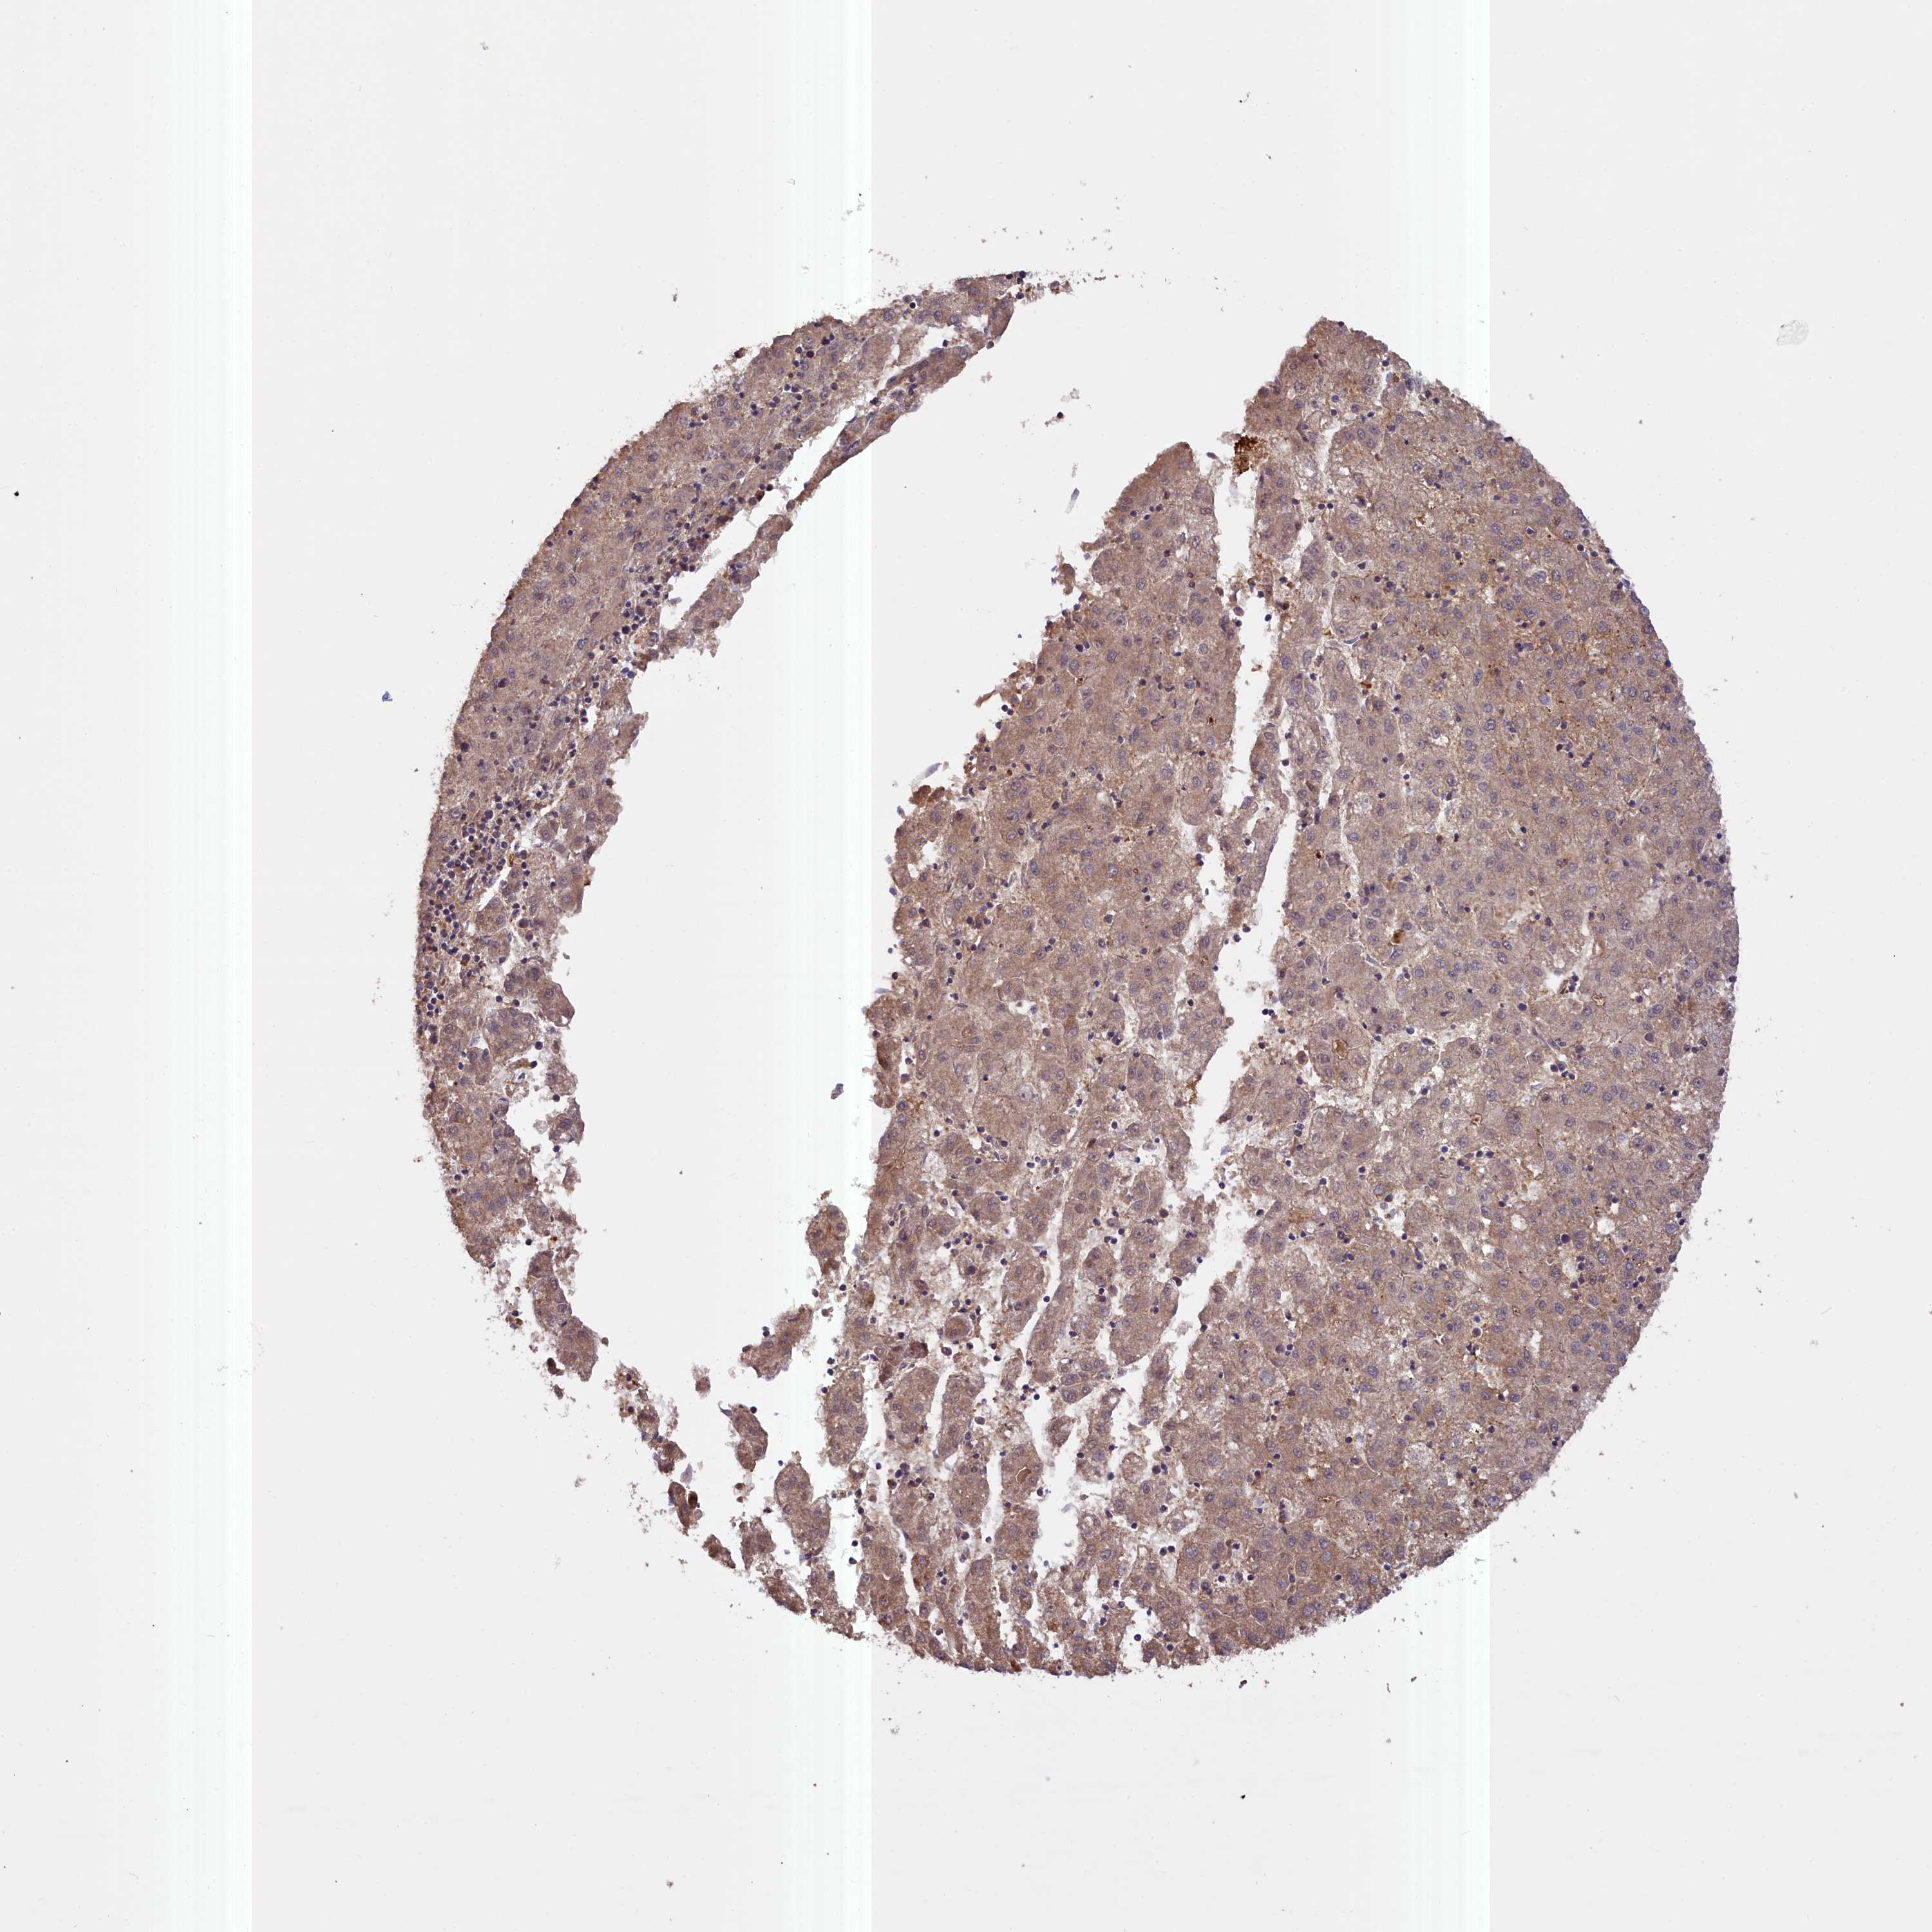

LIVER CANCER - Protein expressioni

A mouse-over function shows sample information and annotation data. Click on an image to view it in a full screen mode. Samples can be filtered based on level of antibody staining by selecting one or several of the following categories: high, medium, low and not detected. The assay and annotation is described here.

Note that samples used for immunohistochemistry by the Human Protein Atlas do not correspond to samples in the TCGA dataset.

Antibody stainingi

Antibody staining in the annotated cell types in the current human tissue is reported as not detected, low, medium, or high, based on conventional immunohistochemistry profiling in selected tissues. This score is based on the combination of the staining intensity and fraction of stained cells.

Each image is clickable and will lead to virtual microscopy that enables deeper exploration of all samples and also displays staining intensity scores, fraction scores and subcellular localization as well as patient and tissue information for each sample.

Antibody HPA041779

Antibody HPA042196

Staining

High

Medium

Low

Not detected

Intensity

Strong

Moderate

Weak

Negative

Quantity

>75%

75%-25%

<25%

None

Location

Nuclear

Cytoplasmic/membranous

Cytoplasmic/membranous,nuclear

Cholangiocarcinoma

Carcinoma, Hepatocellular, NOS